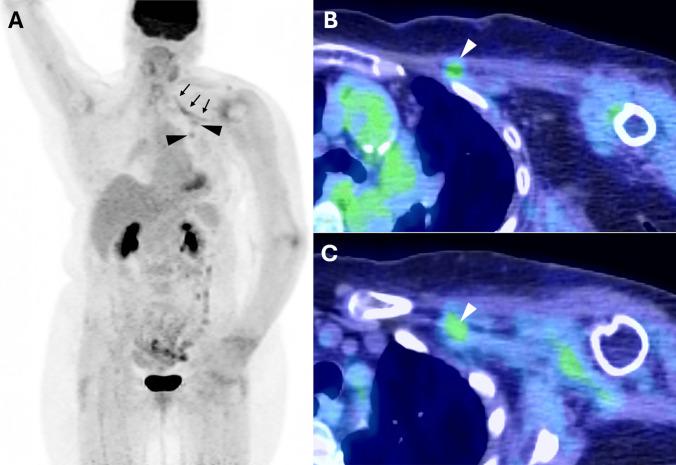

Perineural spread (PNS) of breast carcinoma to the brachial plexus is rare. This study investigates the radiologic features supporting the medial and lateral pectoral nerves (MPN and LPN, respectively) as pathways for PNS of breast cancer to the brachial plexus.

We reviewed 19 patients with biopsy-proven PNS of breast carcinoma to the brachial plexus. All available MRI and F-FDG PET/CT studies were re-evaluated by a musculoskeletal radiologist with expertise in PNS. Imaging features of interest included pectoralis major and minor muscle MRI signal abnormality, abnormal FDG activity, and atrophy; FDG avidity within or along the course of the pectoral nerves; and extent of brachial plexus involvement on MRI and F-FDG PET/CT. Demographic and clinical data were also collected.

All 19 patients had MRI and F-FDG PET/CT scans. Six patients showed clear radiologic evidence of PNS via the pectoral nerves. All six patients demonstrated abnormal MRI signal or enhancement in both the pectoralis major and minor muscles and increased FDG uptake was present in the pectoralis major in 4/6 patients and pectoralis minor in 5/6 patients. Five patients demonstrated atrophy of both the pectoralis major and minor muscles. Increased FDG uptake was noted along the LPN in five patients and the MPN in four. All exhibited brachial plexus enhancement on MRI and increased FDG uptake on PET/CT, supporting contiguous spread from the pectoral nerves.

This study provides radiologic support for the MPN and LPN as a potential pathway for PNS of breast cancer to the brachial plexus. Pectoralis major/minor muscle atrophy, abnormal MRI signal or enhancement, and increased FDG activity within the pectoral muscles and/or along the pectoral nerves may serve as early, non-invasive imaging markers of this process, with potential implications for diagnosis and management.

乳腺癌向臂丛神经的神经周围扩散(PNS)较为罕见。本研究调查支持胸内侧神经和胸外侧神经(分别为MPN和LPN)作为乳腺癌向臂丛神经PNS途径的放射学特征。

我们回顾了19例经活检证实乳腺癌向臂丛神经发生PNS的患者。所有可用的MRI和F-FDG PET/CT研究均由一位在PNS方面有专长的肌肉骨骼放射科医生重新评估。感兴趣的影像特征包括胸大肌和胸小肌的MRI信号异常、FDG活性异常和萎缩;胸神经内或沿胸神经走行的FDG摄取;以及MRI和F-FDG PET/CT上臂丛神经受累的范围。还收集了人口统计学和临床数据。

所有19例患者均进行了MRI和F-FDG PET/CT扫描。6例患者显示出通过胸神经发生PNS的明确放射学证据。所有6例患者胸大肌和胸小肌均表现出异常的MRI信号或强化,4/6例患者胸大肌FDG摄取增加,5/6例患者胸小肌FDG摄取增加。5例患者胸大肌和胸小肌均出现萎缩。5例患者LPN沿线FDG摄取增加,4例患者MPN沿线FDG摄取增加。所有患者MRI上均显示臂丛神经强化,PET/CT上FDG摄取增加,支持从胸神经的连续性扩散。

本研究为MPN和LPN作为乳腺癌向臂丛神经PNS的潜在途径提供了放射学支持。胸大肌/胸小肌萎缩、MRI信号异常或强化以及胸肌内和/或胸神经沿线FDG活性增加可能作为这一过程的早期非侵入性影像标志物,对诊断和管理具有潜在意义。